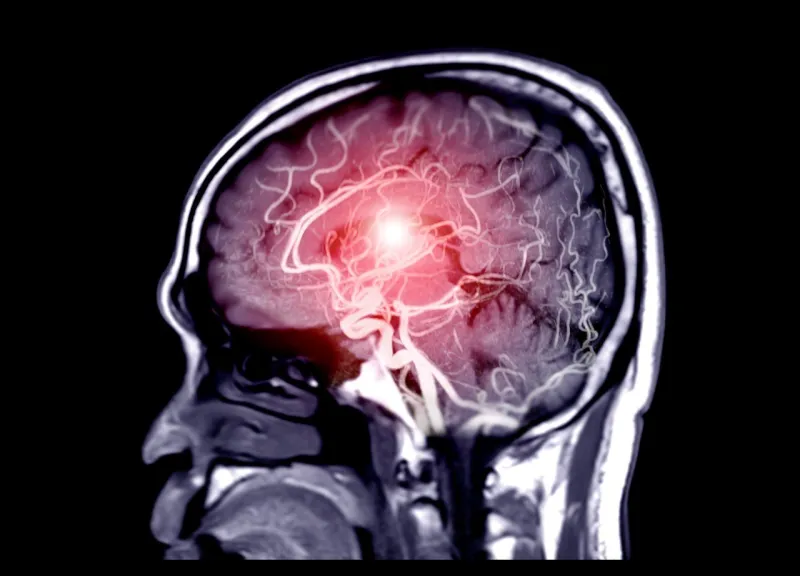

Les tumeurs cérébrales peuvent être bénignes ou malignes. Une tumeur au cerveau n'est donc pas forcément cancéreuse. Elles se distinguent selon leur type, leur localisation et leur caractère primitif ou secondaire. Avec l'Institut National du Cancer, Medisite passe en revue les 9 formes de tumeurs cérébrales.

Une tumeur cérébrale se forme suite à la multiplication anormale de cellules qui constituent une masse, cancéreuse ou non. En effet, un tumeur au cerveau n'est pas systématiquement cancéreuse.

Si elle est bénigne (non cancéreuse), elle aura un développement très lent et ne touchera pas les tissus voisins. Elle pourra être traitée par une simple chirurgie, mais celle-ci dépendra de sa localisation et du risque de séquelles neurologiques définitives. De leurs côtés, les tumeurs malignes primitives, ou cancéreuses, sont adhérentes aux tissus voisins et sont donc plus difficilement accessibles à la chirurgie. Concrètement, le cancer est susceptible de se répandre dans d'autres zones du corps.

Chaque année en France, environ 6 000 personnes sont diagnostiquées avec une tumeur cérébrale primitive. Elles représentent 2 % de l'ensemble des cancers.